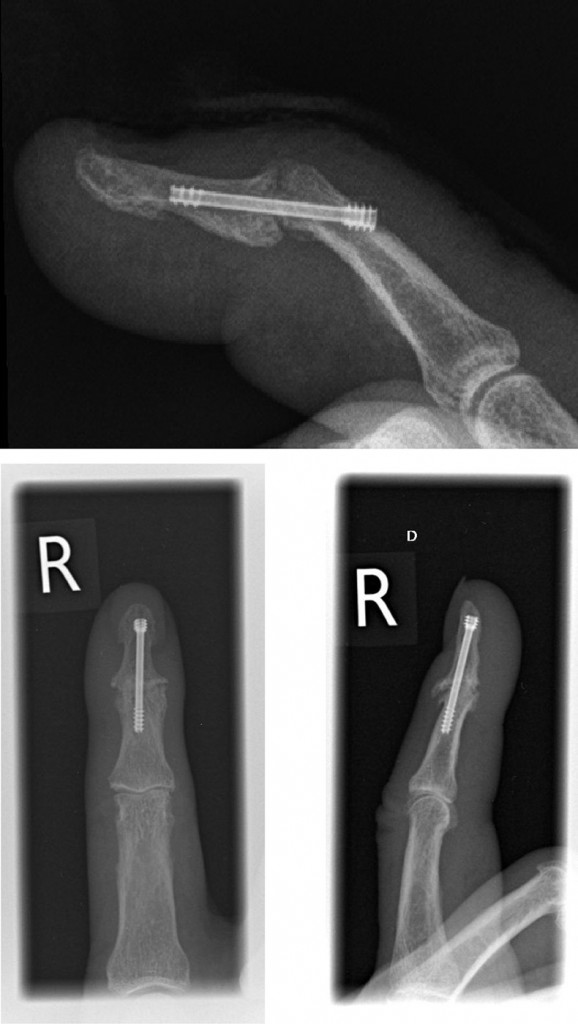

Je nachdem welches Gelenk versteift wurde, resultiert die Versteifung in einem kleineren oder größeren Funktionsdefizit. Hier müssen Versteifungen noch häufiger durchgeführt werden. Lesen Sie alles Wichtige über den Ablauf der Arthrodese, wann sie notwendig ist und welche Risiken sie birgt. Der Eingriff wird bei einer fortgeschrittenen Arthrose durchgeführt, wenn eine Versorgung mit einem künstlichen Gelenk nicht mehr möglich ist.Vorteile einer Arthrodese des Sprunggelenks. Die Arthrodese stellt technisch eine Herausforderung dar und sollte, insbesondere in der Revisionsendoprothetik, aus schließlich von erfahrenen Kniechirurgen durchgeführt werden. Dabei entfernt der Arzt einen der betroffenen Mittelhand-Knochen und ersetzt ihn durch körpereigene Sehnen, etwa die Sehnen des langen Daumenmuskels oder des kurzen Handbeugers. Die beiden Knochenenden werden wie eine Fraktur durch Osteosynthese mit Hilfe von Schrauben, Platten oder Drähten fixiert. 1 Symptome: Gelenkschmerzen und -steifigkeit, Bewegungseinschränkungen, Funktionsstörungen, Schmerzen bei Belastung, Anlaufschmerzen, Verlust der Lebensqualität. Sie umfasst die wichtigsten Anteile des unteren Sprunggelenks: das Gelenk zwischen Sprungbein und Kahnbein (Talonaviculargelenk) und das Gelenk zwischen Sprungbein und . Auch Fehlstellungen der großen Fußzehe, vor allem Hallux valgus und Hallux rigidus, werden in der Regel durch eine Arthrodese in günstiger Gelenkstellung behandelt.

Über den Hautschnitt auf der Innenseite des Fußes wird zum Talonavikulargelenk vorgegangen, das Gelenk wird eröffnet, . 1 Symptome: Gelenkschmerzen und -steifigkeit, . Dies gilt für Menschen mit einem Grad der Behinderung (GdB) von mindestens 50 und einer Wartezeit von mindestens 35 Jahren: Geringfügige Rentenabschläge bei vorzeitigem Renteneintritt Eine frühzeitige Behandlung ist wichtig, um im weiteren Verlauf eine Arthrose zu vermeiden. Inaktiv zu werden kostet Muskelkraft und kann den Abbau des Knorpels beschleunigen.Die Entscheidung , ob es Alternativen zur Sprunggelenkversteifung gibt hängt stark von der vorliegenden Situation ab.Die Arthrodese soll den Patientinnen und Patienten vor allem Lebensqualität zurückgeben und die Schmerzen verringern. Diese Form der Rhizarthrose-Therapie gilt . Eine Arthrose des oberen Sprunggelenks kann eine Indikation für eine Versteifungsoperationen sein.Der Verlauf von Arthrose hängt von der Ursache ab.Eine Spondylodese oder Arthrodese der Wirbelsäule kommt als letzte Möglichkeit bei schweren Erkrankungen mit Instabilität in Betracht, wenn andere Methoden keinen Erfolg bringen.Arthrose ist eine degenerative Gelenkerkrankung, die mit einem starken Knorpelverschleiß einhergeht und den Betroffenen zunehmend Beschwerden bereitet. Arthrose-Knieschmerzen können durch Bewegung und Gewichtsreduktion gelindert werden.Operationsverfahren.